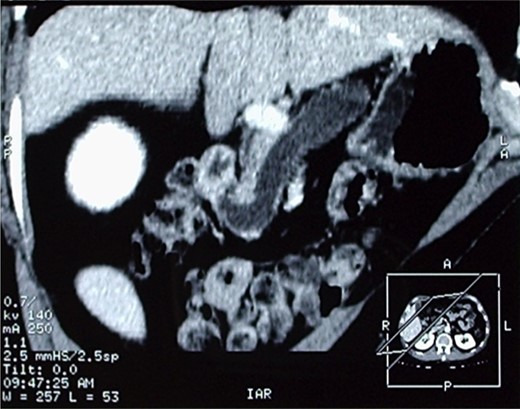

The operative specimen showed a normal thin choledocus (incannulated with a probe) cephalad to a fragile inhomogeneous area corresponding to the tumor (Fig. 4) and an enormously dilated pancreatic duct (held by the forceps) (Fig. 5).

The operative specimen showing a normal thin choledocus (incannulated with a probe) cephalad to the tumor.